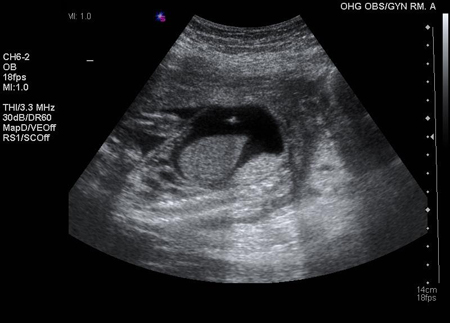

Se o sangue do feto for Rh-negativo ou o fluxo sanguíneo da artéria cerebral média ou os níveis de bilirrubina amniótica permanecerem normais em um feto Rh-positivo, a gestação pode continuar até o termo sem tratamento. Se o sangue do feto for Rh-positivo ou tiver status de Rh desconhecido e se o fluxo da artéria cerebral média ou os níveis de bilirrubina amniótica estiverem elevados, sugerindo anemia fetal, transfusões sanguíneas intrauterinas podem ser administradas ao feto por um especialista em uma unidade equipada para assistência a gestações de alto risco.[Figure caption and citation for the preceding image starts]: Transfusão intraperitoneal; agulha com ponta ecogênica visualizada na bolsa da asciteThe Ottawa Hospital; usado com o consentimento do paciente [Citation ends].